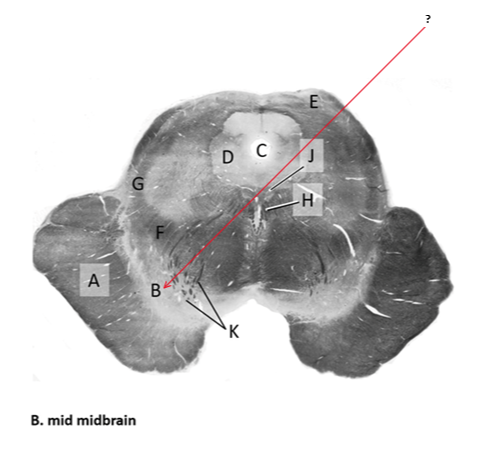

Name this and state its function.

Tectum.

Name this and its divisions+ function?

Substantia nigra.

Cerebral aqueduct.

Crus cerebri.

Medial Lemniscus.

Name this, what is it and state its function.

Lateral lemniscus.

Name this, state its function[2 marks] and how it goes about its function[4 marks].

Medial longitudinal lemniscus.

How?

Oculomotor nucleus.

Name this, state its function[3 marks] and cells involved contributing to function.

Periaqueductal grey.

Root fibres of Oculomotor nerves(CN III).